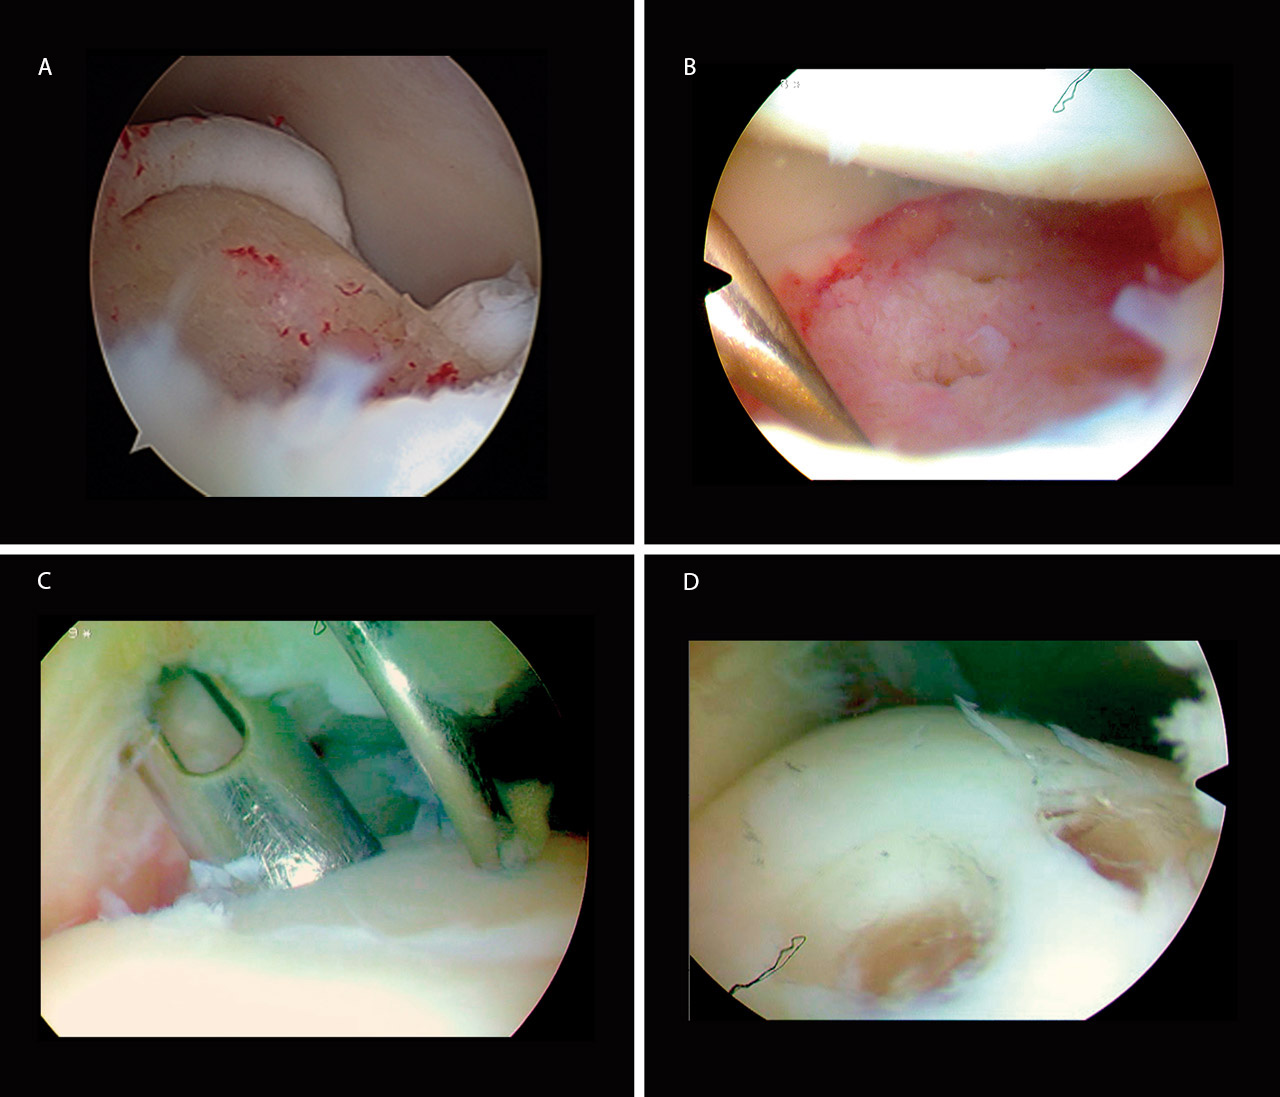

En la visión artroscópica se corroboró la existencia de la lesión encontrada en las Rx y TC prequirúrgicas, desplazada y rotada 180° (Figura 2A).

En primer lugar, se procedió a preparar el lecho óseo del astrágalo mediante desbridamiento con sinoviotomo de los restos de fibrosis y se realizaron varias microperforaciones con el sistema Osteopred® (Figura 2B). Posteriormente, se aplicó tracción no invasiva y, volteándolo dentro de la articulación del tobillo, se consiguió reducir el fragmento a su posición anatómica. Por último, se fijó el fragmento con 2 tornillos reabsorbibles (SmartNail®) (Figuras 2C y 2D) e intraoperatoriamente se comprobó la correcta reducción y el balance articular completo del tobillo.